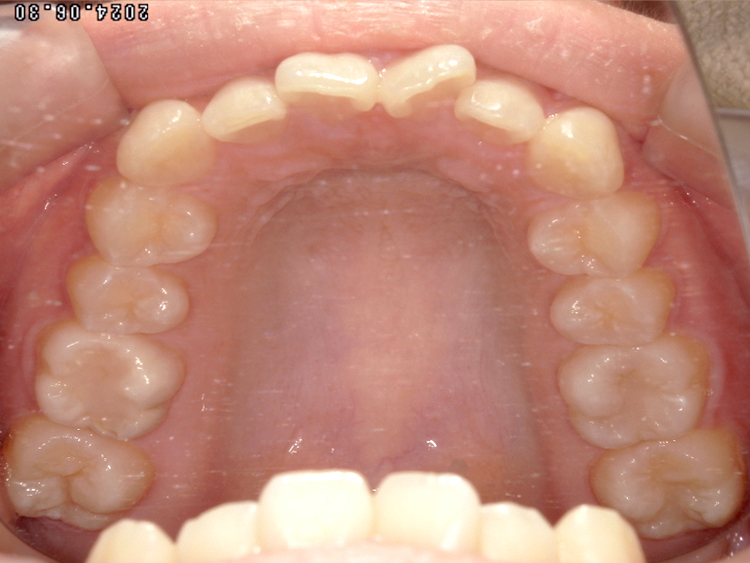

症例3

Before

After

| 主訴 | 上下の歯のガタガタを治したい |

|---|---|

| 年齢 | --- |

| 治療期間 | 約10ヶ月 |

| 治療内容 | インビザラインiGoで上下顎の治療。 狭まっていた歯並びを広げることで、 ガタガタに並んでいた歯を綺麗に並べた。 |

| 治療費 | ¥517,000(税込)+月額調整料 |

| 治療のリスク | 歯と歯の間を削ることでスペースを確保するので、 場合によっては歯が染みる症状が出ることがある。 |